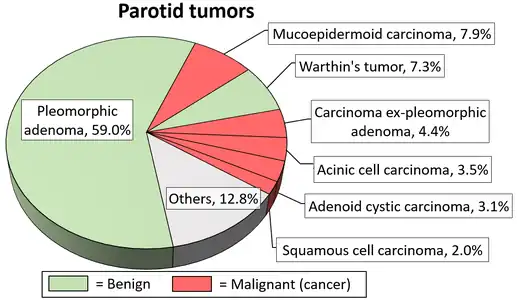

Relative incidence of submandibular tumors, with adenoid cystic carcinoma being the second most common.[17] Relative incidence of parotid tumors, with adenoid cystic carcinoma being relatively rare.[17]

Relative incidence of parotid tumors, with adenoid cystic carcinoma being relatively rare.[17]